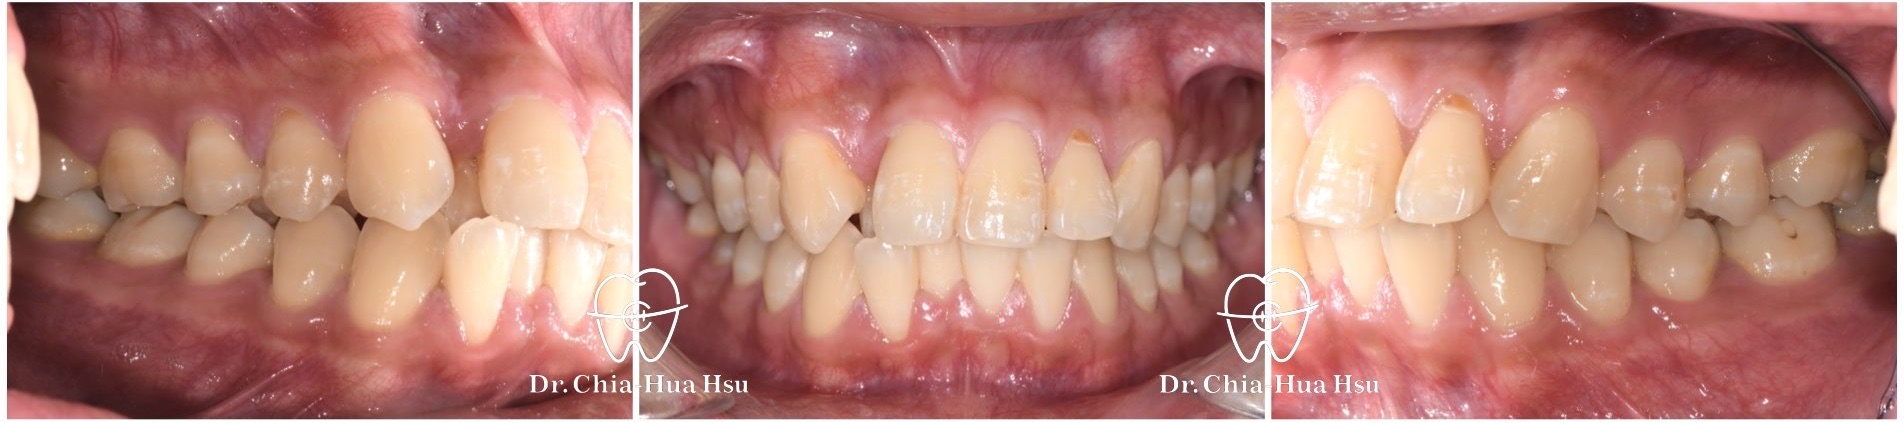

治療前

治療後